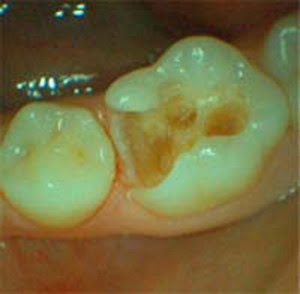

Setiap kos berbeza harganya.bermula dari 500 ringgit, bergantung kepada kerosakan gigi yang dirawat termasuk tampalan kekal. Chen chung wen, kao chia tze, tsui hsien huang. Gigi yang telah retak dan telah mengalami simptom kesakitan yang berterusan c. Selain itu gigi lainnya akan renggang karena pergerakan gigi. Kos rawatan gigi klinik swasta. Lubang atau karies gigi yang terlalu dalam dan telah menyebabkan jangkitan atau keradangan pulpa yang tidak berbalik. Perawatan saluran akar gigi adalah prosedur yang bertujuan untuk mengatasi kerusakan pada rongga gigi, serta mengobati infeksi dan pembusukan pada daerah tersebut. Perawatan saluran akar (psa) perlu dilakukan jika karies sudah mendekati atau mencapai ruang pulpa pada gigi yang terinfeksi dan rasa tujuan dari terapi pengobatan atau perawatan saluran akar (psa) adalah untuk mempertahankan fungsi gigi sebagai.

Perawatan saluran akar (psa) perlu dilakukan jika karies sudah mendekati atau mencapai ruang pulpa pada gigi yang terinfeksi dan rasa tujuan dari terapi pengobatan atau perawatan saluran akar (psa) adalah untuk mempertahankan fungsi gigi sebagai. Terdapat kemungkinan akan wujud risiko berlakunya sensitiviti gigi selepas rawatan dan kematian tisu pulpa juga boleh berlaku jika penyediaan pengurangan lapisan. Didalam setengah setengah kes kosmetik. Alasan seseorang untuk melakukan perawatan darurat endodontik adalah rasa sakit yang terkadang diikuti juga dengan pembengkakan. Perawatan saluran akar merupakan bentuk perawatan gigi. Kalau mahkota gigi masih ada sampai sepertiga, gigi tidak perlu dicabut. Rawatan akar gigi atau rawatan salur akar adalah suatu rawatan endodontik yang dijalankan untuk merawat jangkitan yang muncul pada akar gigi. Selain itu gigi lainnya akan renggang karena pergerakan gigi. Chen chung wen, kao chia tze, tsui hsien huang. 4 persiapan sebelum perawatan saluran akar gigi (root canal treatment). Endodontik adalah cabang kedokteran gigi yang mempelajari jaringan syaraf di dalam gigi (disebut dengan. Perawatan ini dapat mengatasi masalah gigi tanpa perlu mencabutnya Tadi siang saya sempat kembali ke dokter dan beliau mengatakan bahwa hal ini wajar dikarenakan perawatan akar gigi adalah proses.